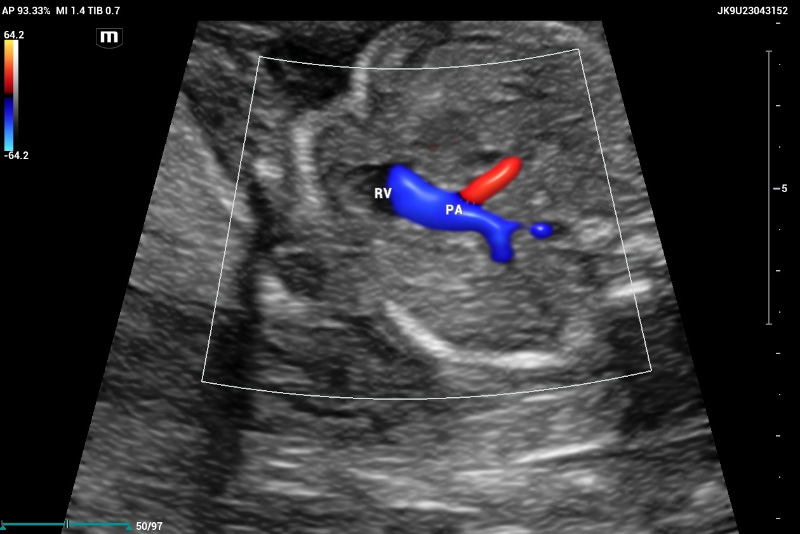

CASE Ultrasound performed on Mindray Resona I9 system. Color doppler showed outflow tract of pulmonary artery (PA) emerging of the right ventricle (RV)

Figure 6. CASE Ultrasound performed on Mindray Resona I9 system. Color doppler showed outflow tract of pulmonary artery (PA) emerging of the right ventricle (RV)